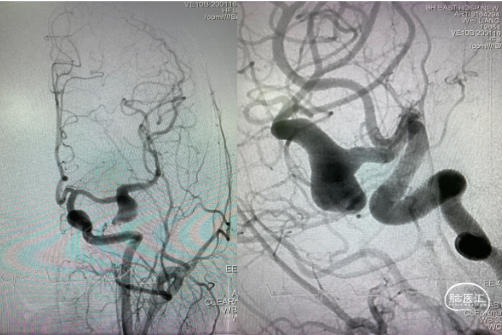

术后造影

1. 大型或巨大形动脉瘤,尤其梭形宽颈动脉瘤单纯弹簧圈栓塞后复发率较高;Pipeline™ 血流导向密网支架治疗可大大减少动脉瘤的复发;由于瘤颈较宽,可先进行瘤内部分栓塞,通过弹簧圈的填塞为血流导向密网支架提供一定的支撑,防止其在瘤腔内摆动,从而起到更好的血流导向作用,同时可降低密网支架释放过程中疝入动脉瘤的概率。

3. 支架完全释放后,观察打开及贴壁良好,再逐步致密填塞动脉瘤,通过进一步填塞弹簧圈降低破裂风险。